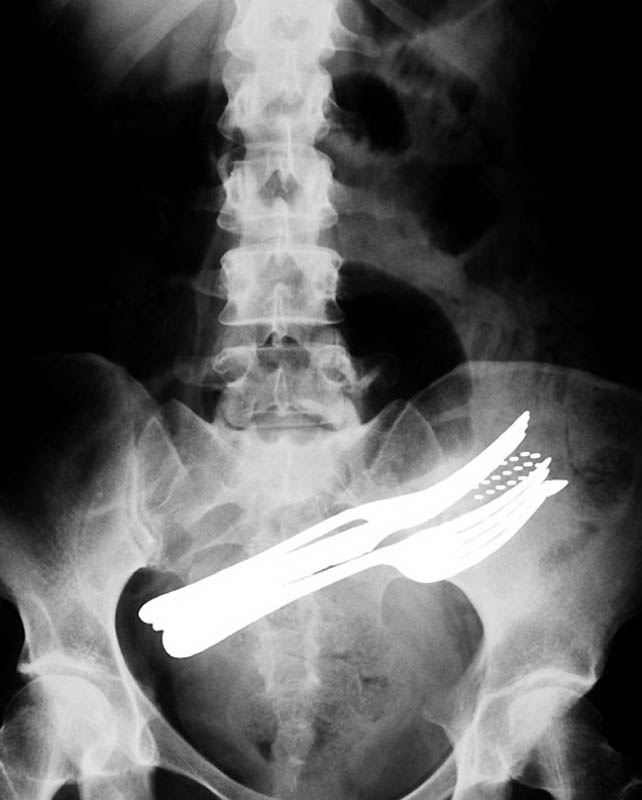

Живот пациента, который проглотил две вилки, шариковую ручку и зубную щетку.